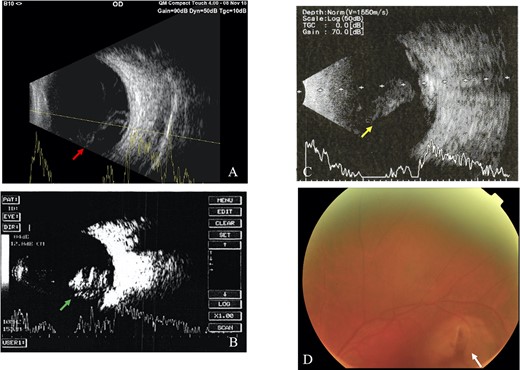

All IOFBs were successfully identified using slit-lamp biomicroscopy, fundus examination, B-scan ultrasonography, plain orbital X-ray, and viewed intraoperatively. Most foreign bodies were intravitreal (four patients, Fig. 1), followed by intraretinal (two patients, Fig. 2), intralenticular (two patients, Fig. 3) and intracorneal (one patient, Fig. 4).

Intraretinal foreign body; (A) B-scan ultrasound revealed hazy vitreous with absence of retinal detachment and high reflective intravitreal object (red arrow), suggestive of metallic IOFB and endophthalmitis (Case 3), (B) Fundus examination showed a foreign body at inferior temporal quadrant of the LE (white arrow), with intraretinal hemorrhage (Case 4).